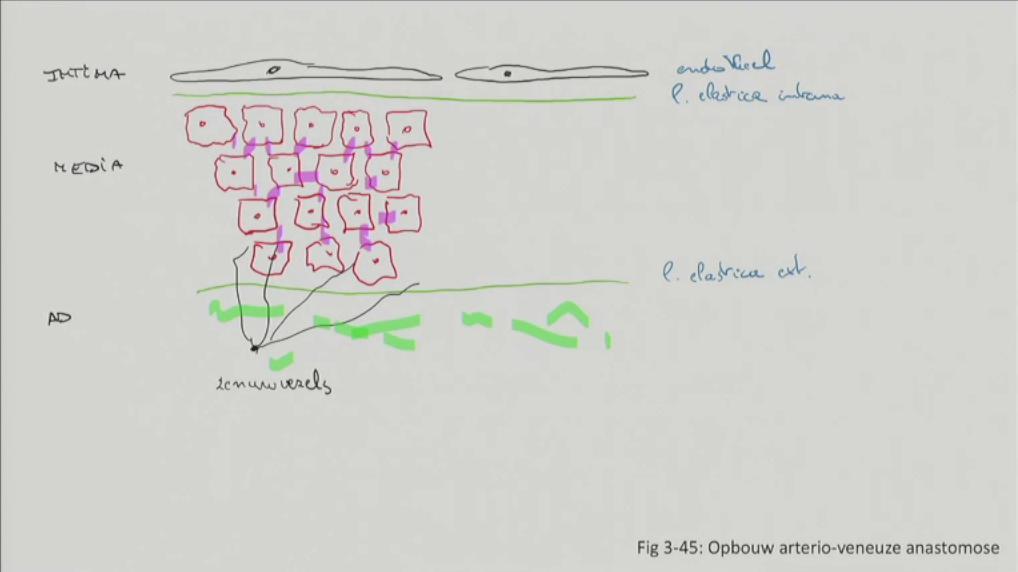

Fig 3.45: Opbouw van arterio-veneuze anastomose

|

N/A |